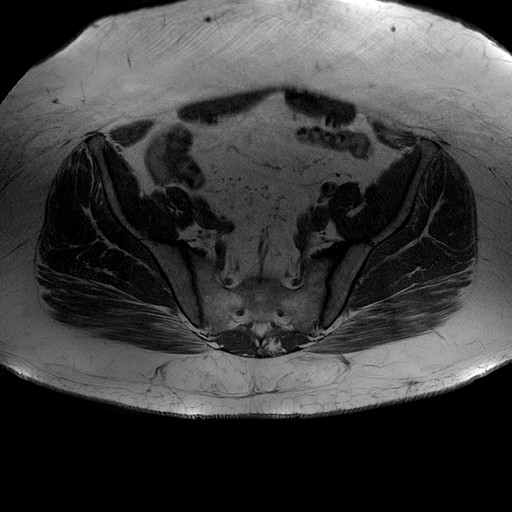

Esami: RMN BACINO

T1W_TSE

Evidenti e simmetriche alterazioni osteofitosiche in regione coxo femorale con riduzione delle rime articolari. Degenerazione completa del cercine glenoideo. Non attuali segni di versamento articolare. Non segni di edema osseo che escludono attuale algodistrofia od osteonecrosi. Lieve e simmetrica riduzione del trofismo della muscolatura glutea.